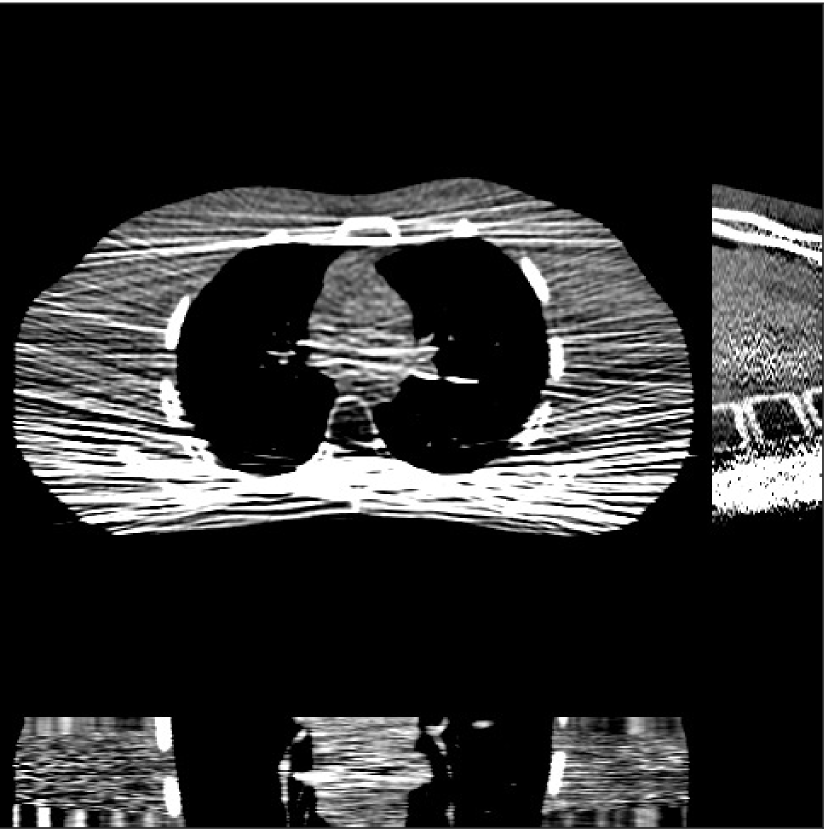

We used the pre-learned union of 15 square transforms from the XCAT phantom simulations to reconstruct the synthesized helical chest scan volume of size 420×420×222420420222{420\times 420\times 222} with Δx=Δy=1.1667subscriptΔ𝑥subscriptΔ𝑦1.1667\Delta_{x}=\Delta_{y}=1.1667 mm and Δz=0.625subscriptΔ𝑧0.625{\Delta_{z}=0.625} mm. The sinograms were of size 888×64×3611888643611888\times 64\times 3611. Since the clinical data is synthesized via the PWLS-ULTRA reconstruction, the noise model for this synthesized data is obscure, making it difficult to determine appropriate low-dose levels for such data. We tested the radiation dose of I0=1×104subscript𝐼01superscript104I_{0}=1\times 10^{4} with an electronic noise variance the same as the XCAT phantom simulation, i.e., σ2=25superscript𝜎225\sigma^{2}=25. The percentage of non-positive pre-log measurements for the synthesized clinical data in this case was around 0.14%percent0.140.14\%. Such non-positive values were replaced by 1×1051superscript1051\times 10^{-5} for PWLS-based methods. Fig. 8(a) shows the “true” clinical image that was reconstructed from real clinical regular-dose sinogram using the PWLS-ULTRA method.

Refer to caption

(a)

(b)

Figure 8: (a) “true” clinical image (HU), (b) the reconstruction (HU) of the synthesized data with PWLS-EP for I0=1×104subscript𝐼01superscript104I_{0}=1\times 10^{4} with βep=215subscript𝛽𝑒𝑝superscript215\beta_{ep}=2^{15}. The central axial, sagittal, and coronal slices of the volume are shown.

Figure 9: Reconstructed images (columns 1 to 3) and the image profiles (the 4th column) along the green line in the “true” clinical image for the synthesized clinical data with I0=1×104subscript𝐼01superscript104I_{0}={\color[rgb]{0,0,0}1\times}10^{4} and σ2=25superscript𝜎225\sigma^{2}=25. (a) Results for axial slice No. 67, (b) results for slice No. 90, and (c) results for slice No. 120. We selected one ROI for each of these three slices and the arrows point out some small structures in the image. The display windows for reconstructed images are [800, 1200] HU, and those for the zoomed-in ROIs are [950, 1200] HU.

Similar to the XCAT phantom simulation, the initial image for both SPULTRA and PWLS-ULTRA was a reconstruction obtained using PWLS-EP. We set the regularizer parameter βepsubscript𝛽𝑒𝑝\beta_{ep} for PWLS-EP to 215superscript2152^{15} to generate a smoother (with less noise) initial image, which led to good visual image equality for the SPULTRA and PWLS-ULTRA reconstructions. Since the optimization problem for PWLS-EP is strictly convex, we simply initialized PWLS-EP with a zero image. Fig. 8(b) shows the PWLS-EP reconstructed image for I0=1×104subscript𝐼01superscript104I_{0}=1\times 10^{4}. We set the regularizer parameters for both PWLS-ULTRA and SPULTRA as γc=5×104subscript𝛾𝑐5superscript104\gamma_{c}=5\times 10^{-4}, and β=1.5×104𝛽1.5superscript104\beta=1.5\times 10^{4}.

V-B2 Reconstruction results for the synthesized clinical data

Fig. 9 shows three axial slices from the 3D reconstructions with SPULTRA and PWLS-ULTRA at I0=1×104subscript𝐼01superscript104I_{0}=1\times 10^{4}: the middle slice (No. 67) and two slices located farther away from the center (No. 90 and No. 120). The image profiles along a horizontal line (shown in green) in the displayed slices are also shown in Fig. 9. The reconstructed slices using PWLS-ULTRA appear darker around the center compared to the “true” clinical image and the reconstructions with SPULTRA. This means PWLS-ULTRA produces a strong bias in the reconstruction. The bias can be observed more clearly in the profile plots: the pixel intensities for the SPULTRA reconstruction better follow those of the “true” clinical image, while those for the PWLS-ULTRA reconstruction are much worse than the “true” values. Moreover, SPULTRA achieves sharper rising and failing edges compared to PWLS-ULTRA. In other words, SPULTRA also achieves better resolution than PWLS-ULTRA. Fig. 9 also shows a zoomed-in ROI for each of the chosen slices, and highlights some small details with arrows. It is clear that in addition to reducing the bias, SPULTRA reconstructs image details better than PWLS-ULTRA.